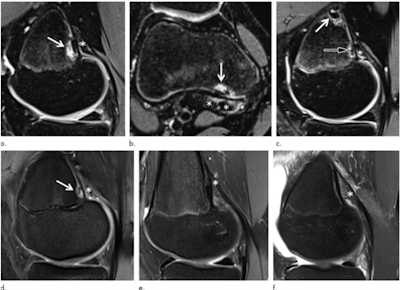

Images show examples of (a-d) DFCI at the tendon attachment of the medial head of the gastrocnemius muscle [MHG] and (e, f) knees without DFCI. Sagittal (a) and axial (b) fat-suppressed T2-weighted MRI scans in a 14-year-old female competitive skier show a 5-mm DFCI (arrow) at the distal MHG attachment (*). (c) Sagittal fat-suppressed T2-weighted MRI scan in another 14-year-old female competitive skier shows simultaneous DFCIs at the proximal (8 mm; white arrow) and distal (4 mm; black arrow) part of the MHG tendon attachment (*). (d) Sagittal fat-suppressed proton density-weighted MRI scan in a 14-year-old female control participant shows a 4-mm DFCI (arrow) at the distal MHG attachment (*). Sagittal fat-suppressed proton density-weighted MRI scans in 15-year-old female control participant (e) and 15-year-old male control participant (f) without a DFCI for comparison. The broad and fan-shaped appearance of the proximal MHG tendon (*) is especially well visualized in (f) because of edematous demarcation after knee trauma. Caption and images courtesy of the RSNA.Stern and colleagues hope the findings will help young patients with DFCI avoid invasive diagnostic procedures.